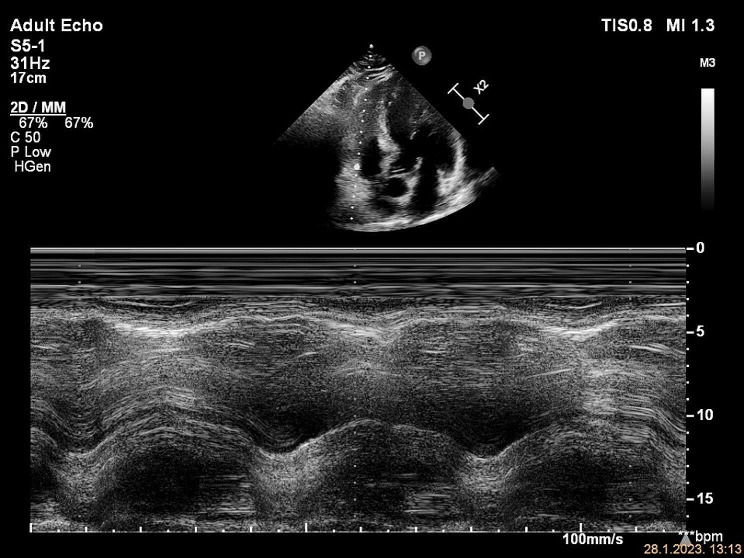

Case presentation: In this case series, we demonstrate a typical ESN pattern on RVOT Doppler evaluation in three patients with intermediate-risk PE presenting to our emergency department (ED). None of the patients had been previously diagnosed with pulmonary hypertension or other chronic pulmonary and cardiac disease. The pre-test probability was low. Massive proximal emboli were found on CT angiograms, involving pulmonary truncus or main pulmonary arteries. Previously, the ESN pattern was identified on a focused echocardiogram, which was the only echocardiographic indicator of increased pulmonary vascular resistance.